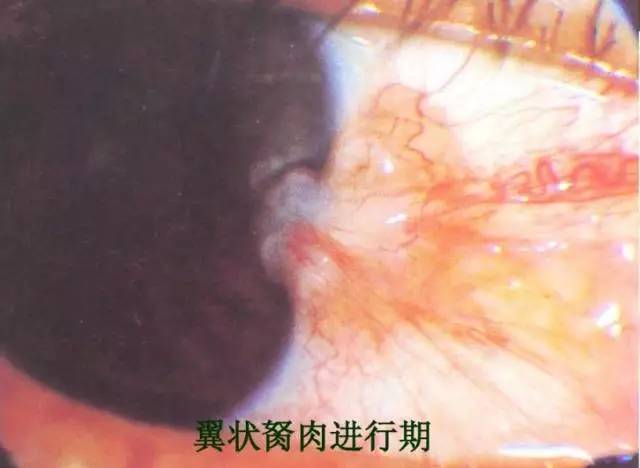

进展型: 胬肉的颈部宽大,新(xīn)生血管多(duō),充血,肥厚,體(tǐ)部呈三角形向两侧伸展,头部明显隆起,長(cháng)入黑眼珠表面,甚至遮挡瞳孔。